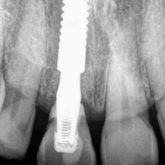

He received his Diploma in Implantology in 2016 from the University of Pretoria, which he passed with Distinction. He is also a member of the International Team for Implantology (ITI), which is based in Switzerland and offers members access to the latest research and cutting-edge techniques.